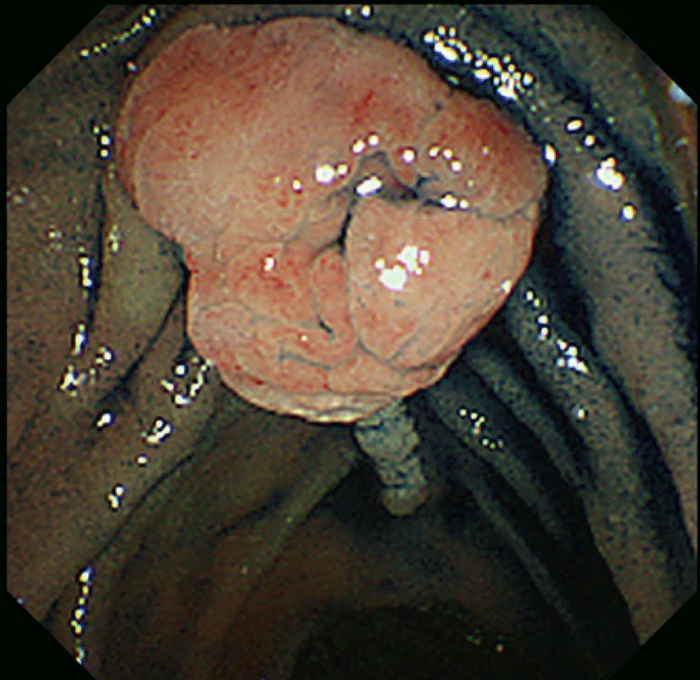

- 胃底腺ポリポーシス(図Ⅱ-6)は健常人にみられる胃底腺ポリープとは数や大きさが異なり特徴的で,FAP症例の88%にみられ73),補助診断として参考になる。

- 胃底腺ポリポーシスの中に腺腫(図Ⅱ-7),および癌が発生しうる。

図Ⅱ-6 胃底腺ポリポーシス